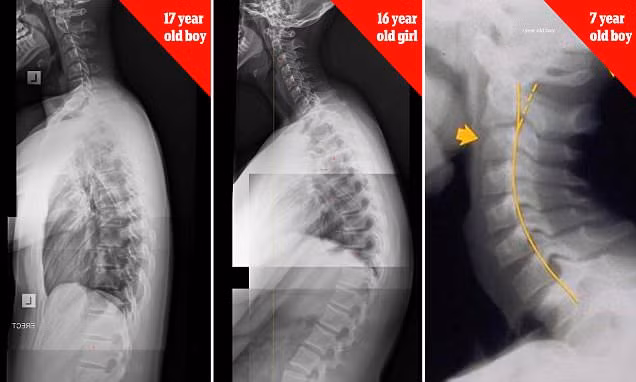

Những hình ảnh chup X-quang cho thấy trẻ em từ 7 tuổi cho đến thanh thiếu niên có xương cổ và cột sống biến dạng nghiêm trọng do suốt ngày chúi mặt vào điện thoại thông minh.

Hình X-ray cột sống của một cô gái 16 tuổi bị cong hình chữ S do hiệu ứng cúi xuống nhìn điện thoại.